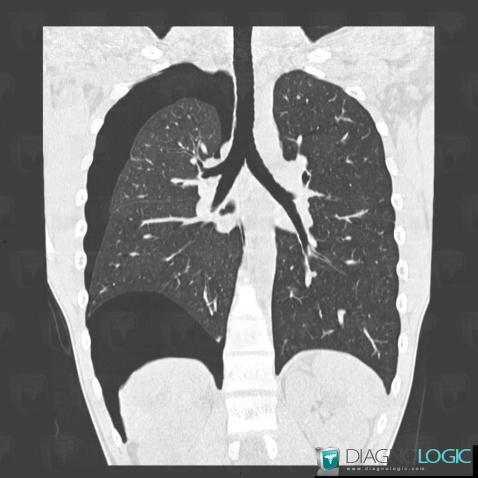

Pneumothorax, Plèvre, Scanner

Voici les informations spécifiques à l'image clé ci dessus:

- Diagnostic Pneumothorax, Localisation(s) Plèvre, comportant les gammes